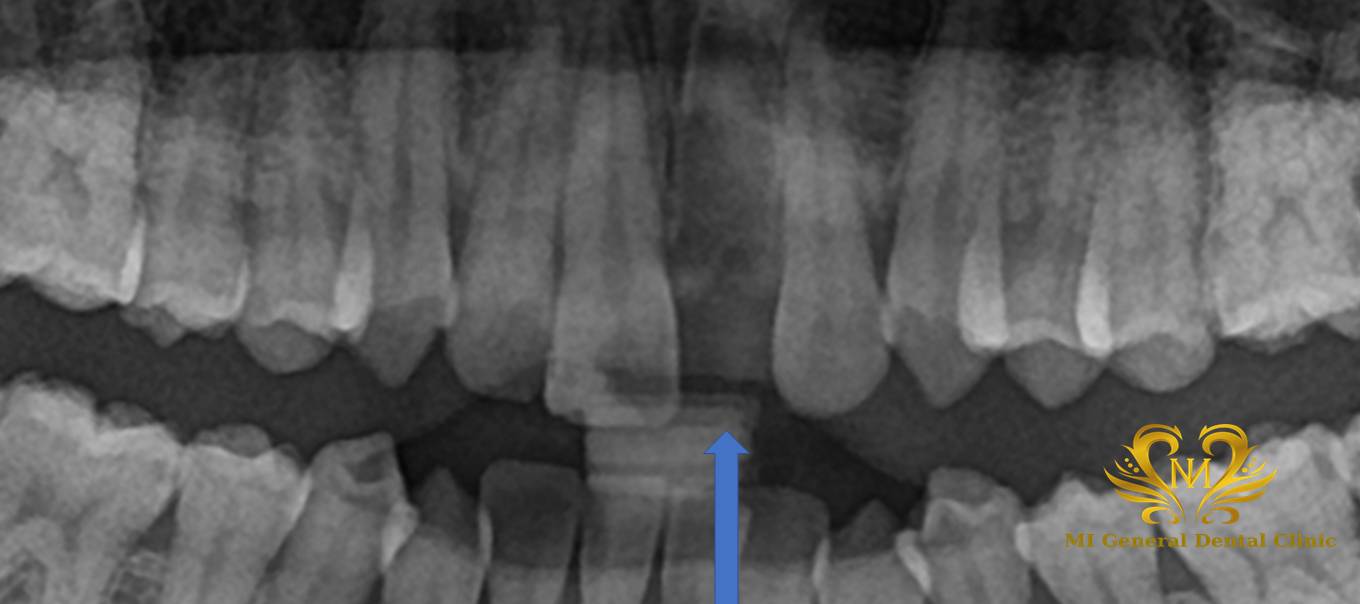

事故により前歯を無くし、インプラント治療をご希望で来院されたケース

治療前

事故により左上前歯を完全脱臼し、インプラントについてのお話を希望され来院。

初診時ご自身の歯を仮歯として使えるよう調整をし、インプラントについてコンサル準備を進めた。

初診時には、現在のお口の状態を詳しく確認するため、レントゲン撮影や口腔内の診査を行いました。当院では検査結果をもとに、後日あらためて院長によるコンサルテーション(治療説明)のお時間を設けています。